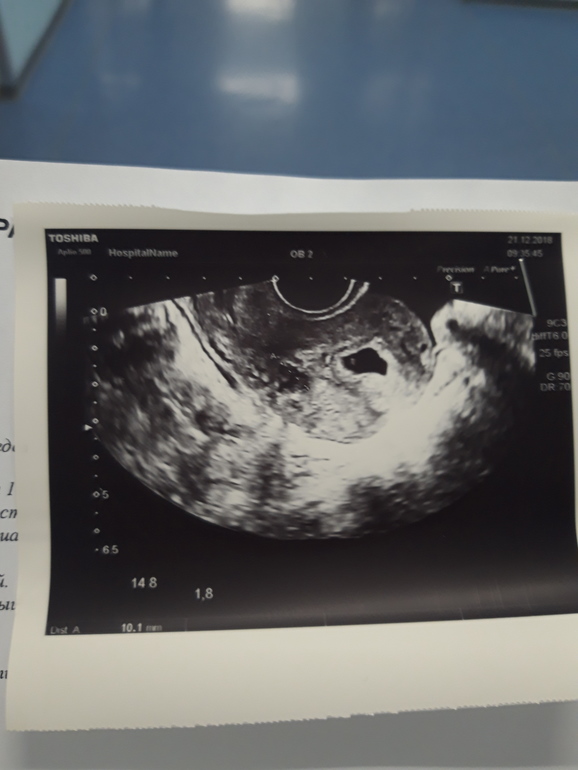

Фоточку с узи прикрепляю.

Беременность- 1 триместр ( только до 10 недель)В продолжение к этому ( https://m.babyblog.ru/community/post/conception/3422085 ) к вечеру начались режущие боли в районе желудка,забрали по скорой в больницу с подозрением на панкреотит. Уже 3 раза взяли кровь из вены,ночью ставили капельницу "стерофундин" , с утра сделали гастэроскопию(ощущения не из приятных,но я пережила) заключение "поверхностный гастрит" ; "дуодено-гастральный рефлюкс" . Объяснять как обычно никто ничего не стал,кушать не дают,пить разрешили только воду,сделали узи. По результатам: "плодное яйцо 7.5 мм в матке,эмбриона пока не видно,прогрессирующая беременность 5 недель,миома матки 1 см( откуда она взялась ети ее за ногу?!)" Узи сказали повторить в конце следующей недели чтобы можно было рассмотреть эмбрион. Лежу,жду что будет дальше. Хочу чтобы тянущие боли прекратились,покушать и домой к мужу😔